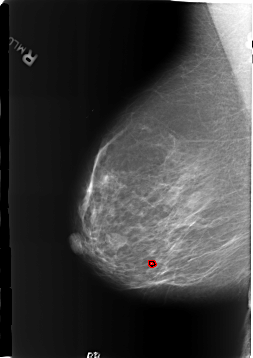

B_3186_1.RIGHT_MLO

RIGHT_MLO LINES 5720 PIXELS_PER_LINE 4040 BITS_PER_PIXEL 12 RESOLUTION 50 OVERLAY

FILE: B_3186_1.RIGHT_MLO.OVERLAY

TOTAL_ABNORMALITIES 1

ABNORMALITY 1

LESION_TYPE CALCIFICATION TYPE LUCENT_CENTER DISTRIBUTION N/A

ASSESSMENT 2

SUBTLETY 4

PATHOLOGY BENIGN_WITHOUT_CALLBACK

TOTAL_OUTLINES 1

BOUNDARY